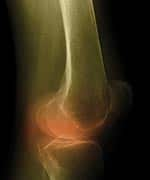

Cola Intake May Decrease Bone Density in Women | |

Daily consumption of cola beverages is associated with decreased bone mineral density of the hip in older women, according to just-released findings.10 Researchers examined dietary intake and hip and spine bone mineral density in more than 2,500 men and women in their fifties and sixties. After adjusting for body mass index, height, age, energy intake, physical activity level, smoking, menopausal status, and estrogen use (in women only), and intake of alcohol, caffeine, vitamin D, and calcium, they found that cola intake in women was associated with significantly lower bone mineral density of the hip. Drinking one daily serving of cola decreased a woman’s bone density by 4-5%, while consuming non-cola carbonated beverages had no effect on bone density.10 Phosphoric acid in cola may slowly leach calcium from the bones, decreasing their density.11 —Elizabeth Wagner, ND | |